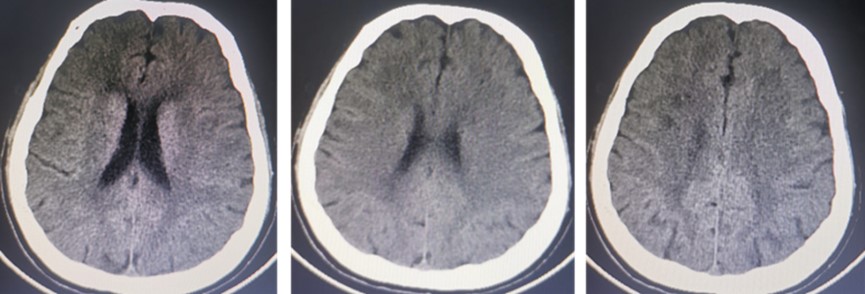

结合上述分析,我们考虑可能为CIE所致;返回神经内科病房后我们立刻给予患者激素保护血脑屏障,甘露醇脱水减轻脑细胞水肿,大量补液水化等对症治疗。术后24h复查头颅CT示左侧大脑半球广泛高密度影完全消失(图4)。患者神志及右侧肢体无力等症状逐渐好转,进一步证实了CIE的诊断。术后3d患者症状完全消失,无任何后遗症。

图4 术后第1d颅脑CT 显示颅内多发高密度影消失